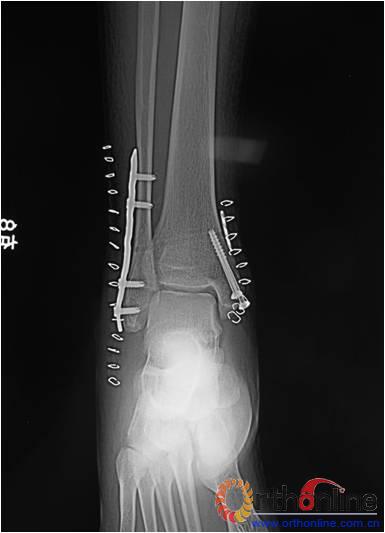

本组患者均获得随访,随访时间为6~12个月,平均9个月。所有患者切口I期愈合。随访采取美国足踝外科协会评分 [American Orthopedic Foot and Ankle Society (AOFAS) hindfoot and ankle scores]评定踝关节功能(76~94分,平均87.3分)。随访患者均拍摄双侧踝关节正侧位X线片(图3),并对其进行测量。X线示:术后患侧下胫腓间隙平均为3.8mm(3~5mm)。本组患者中未发生术后下胫腓关节间隙再次增宽以及骨间缝合线再次手术取出。无感染,血管神经损伤及内固定失败等并发症。

a

b

3 a. 术前患者踝关节X线片,可见下胫腓关节间隙增宽;b. 术后患者踝关节X线片,未见下胫腓关节分离现象